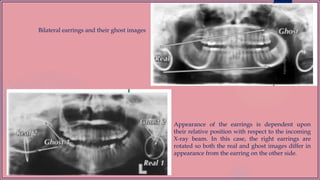

Bilateral earrings and their ghost images

Appearance of the earrings is dependent upon

their relative position with respect to the incoming

X-ray beam. In this case, the right earrings are

rotated so both the real and ghost images differ in

appearance from the earring on the other side.